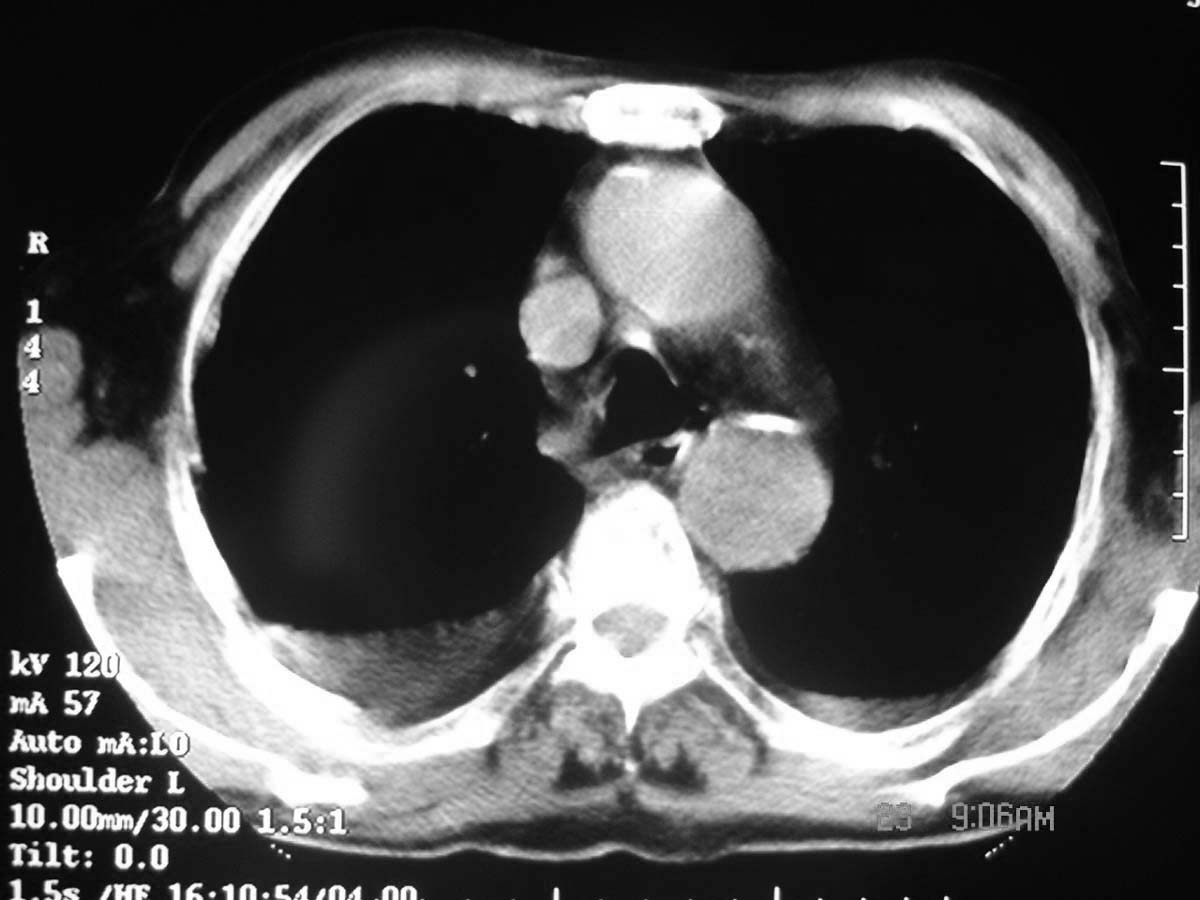

以下是引用守望可可西里在2006-11-23 14:33:00的发言:[br][br] 糖尿病病人很容易继发结核,病人又有双侧胸膜增厚、粘连、胸腔积液以及双上肺的斑片状、条索状影结核病灶影,以一元论考虑,右下肺病变首先考虑干酪性肺炎,可以正规抗炎治疗后复查,排除一般的肺炎。